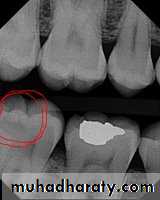

Radiograph of occlusal caries. This radiograph shows (1) severe occlusal caries, which appears as a large radiolucent lesion in the first molar

• Dental Caries

Radiograph of buccal or lingual caries. Buccal or lingual caries on this mandibular second premolar appears as a round radiolucency (superimposed over the pulp chamber)

Radiograph of recurrent caries. This radiograph shows (1) radiolucent caries under the metallic restoration

Dental Recurrent Caries